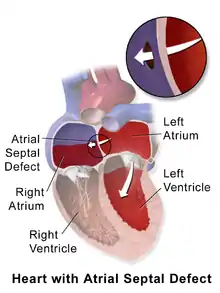

Heart of human embryo of about 35 days Atrial septal defect with left-to-right shunt

Atrial septal defect with left-to-right shunt Illustration depicting atrial septal defect

Illustration depicting atrial septal defect